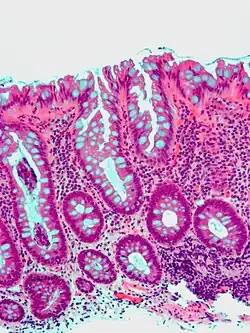

| Tubular adenoma | 2% at 1.5 cm[12] | Low to high grade dysplasia[13] | Over 75% of volume has tubular appearance.[14] |

|

Adenomas

Neoplastic polyps of the bowel are often benign hence called adenomas. An adenoma is a tumor of glandular tissue, that has not (yet) gained the properties of cancer.

The common adenomas of the colon (colorectal adenoma) are the tubular, tubulovillous, villous, and sessile serrated (SSA).[18] A large majority (65–80%) are of the benign tubular type with 10–25% being tubulovillous, and villous being the most rare at 5–10%.[9]

- Tubular adenoma: 5% risk of cancer

Micrograph of a tubular adenoma, the most common type of dysplastic polyp in the colon

Micrograph of a tubular adenoma, the most common type of dysplastic polyp in the colon -

Micrograph of a tubular adenoma – dysplastic epithelium (dark purple) on left of image; normal epithelium (blue) on right. H&E stain.

Micrograph of a tubular adenoma – dysplastic epithelium (dark purple) on left of image; normal epithelium (blue) on right. H&E stain. -